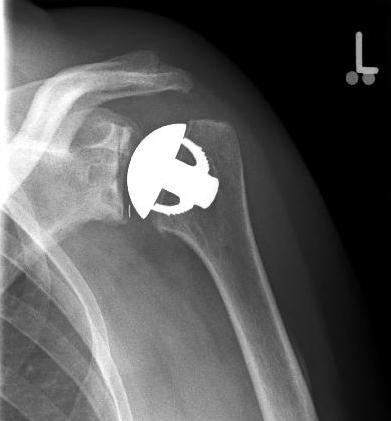

Special prostheses such as an inverse shoulder prosthesis (syn.: "Delta prosthesis", "Grammont prosthesis") for the combination of severe omarthrosis with joint instability and rotator cuff defects

Right: radiograph of an inverse shoulder prosthesis for rotator cuff defect arthropathy.